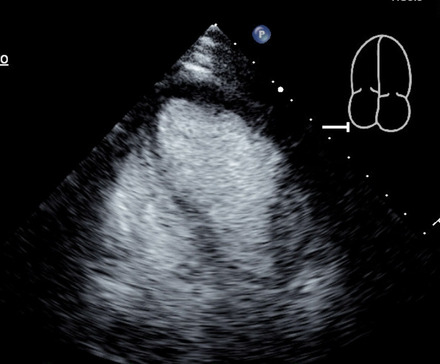

Case: A 76-year-old female presented with typical chest pain, nausea, and worsening shortness of breath. On examination, she was hypotensive and cold to touch. EKG showed T-wave inversions in lateral leads with elevated cardiac troponins. Coronary angiogram showed non-obstructive coronary artery disease, and right heart catheterization revealed elevated filling pressures. Transthoracic echocardiogram (TTE) showed septal hypertrophy and SAM of the mitral valve causing dynamic LVOT obstruction (Figure 1) and ejection fraction (EF) of 20%. TTE with contrast showed apical ballooning consistent with TC (Figure 2).